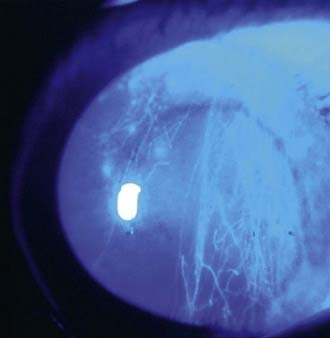

image

Figure 627-1 The injured eye.

(From Khaw PT, Shah P, Elkington AR: Injury to the eye, BMJ 328:36–38, 2004.)